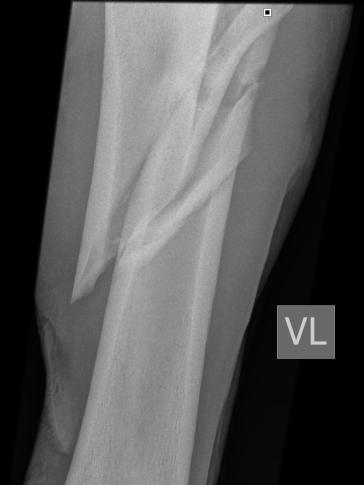

Frakturen (Knochenbrüche) und Fissuren (feine Risse im Knochen) entstehen beim Pferd meist durch Stürze, Ausrutschen, Schlagverletzungen, Kollisionen oder Überbelastung. Bei Verdacht sollte das Pferd möglichst wenig bewegt und sofort tierärztlich untersucht werden. Eine Röntgenuntersuchung ist notwendig, um die Diagnose zu sichern. Fissuren sind im Röntgenbild allerdings häufig erst nach etwa zehn Tagen erkennbar. Besteht der Verdacht auf eine Fissur, sind konsequente Boxenruhe und eine Kontrolluntersuchung nach rund zehn Tagen besonders wichtig.

Viele Frakturen erfordern eine chirurgische Stabilisation in einer spezialisierten Klinik. In ausgewählten Fällen ist eine konservative Behandlung an einer Klinik möglich mit Stabilisation im Netz. Dazu zählen beispielsweise bestimmte Beckenfrakturen oder nicht verschobene Frakturen langer Röhrenknochen. Die Entscheidung über die geeignete Therapie wird stets individuell nach genauer Diagnostik getroffen.

Fraktur eines langen Röhrenknochens

Grundsätzlich unterscheidet man zwischen inkompletten und kompletten Frakturen. Inkomplette Frakturen werden als Fissuren bezeichnet. Komplette Frakturen können einfach sein, mit wenigen Fragmenten, oder komplex, wenn mehrere Knochenstücke entstanden sind. Eine weitere wichtige Einteilung betrifft die Haut: Ist sie intakt, spricht man von einer geschlossenen Fraktur. Ist der Knochen sichtbar, handelt es sich um eine offene Fraktur. Diese Unterscheidungen sind entscheidend für Therapie und Prognose.

Die Heilungsaussichten hängen von verschiedenen Faktoren ab, unter anderem vom Alter und Gewicht des Pferdes, der Art und Lage der Fraktur, möglichen Begleitverletzungen sowie vom anschließenden Management. Offene Frakturen haben aufgrund der Infektionsgefahr meist eine vorsichtigere Prognose als geschlossene. Komplexe Mehrfragment-frakturen heilen in der Regel schwieriger als einfache Brüche. Leichtere Pferde wie Ponys oder Fohlen haben durch die geringere Belastung häufig bessere Heilungsaussichten.